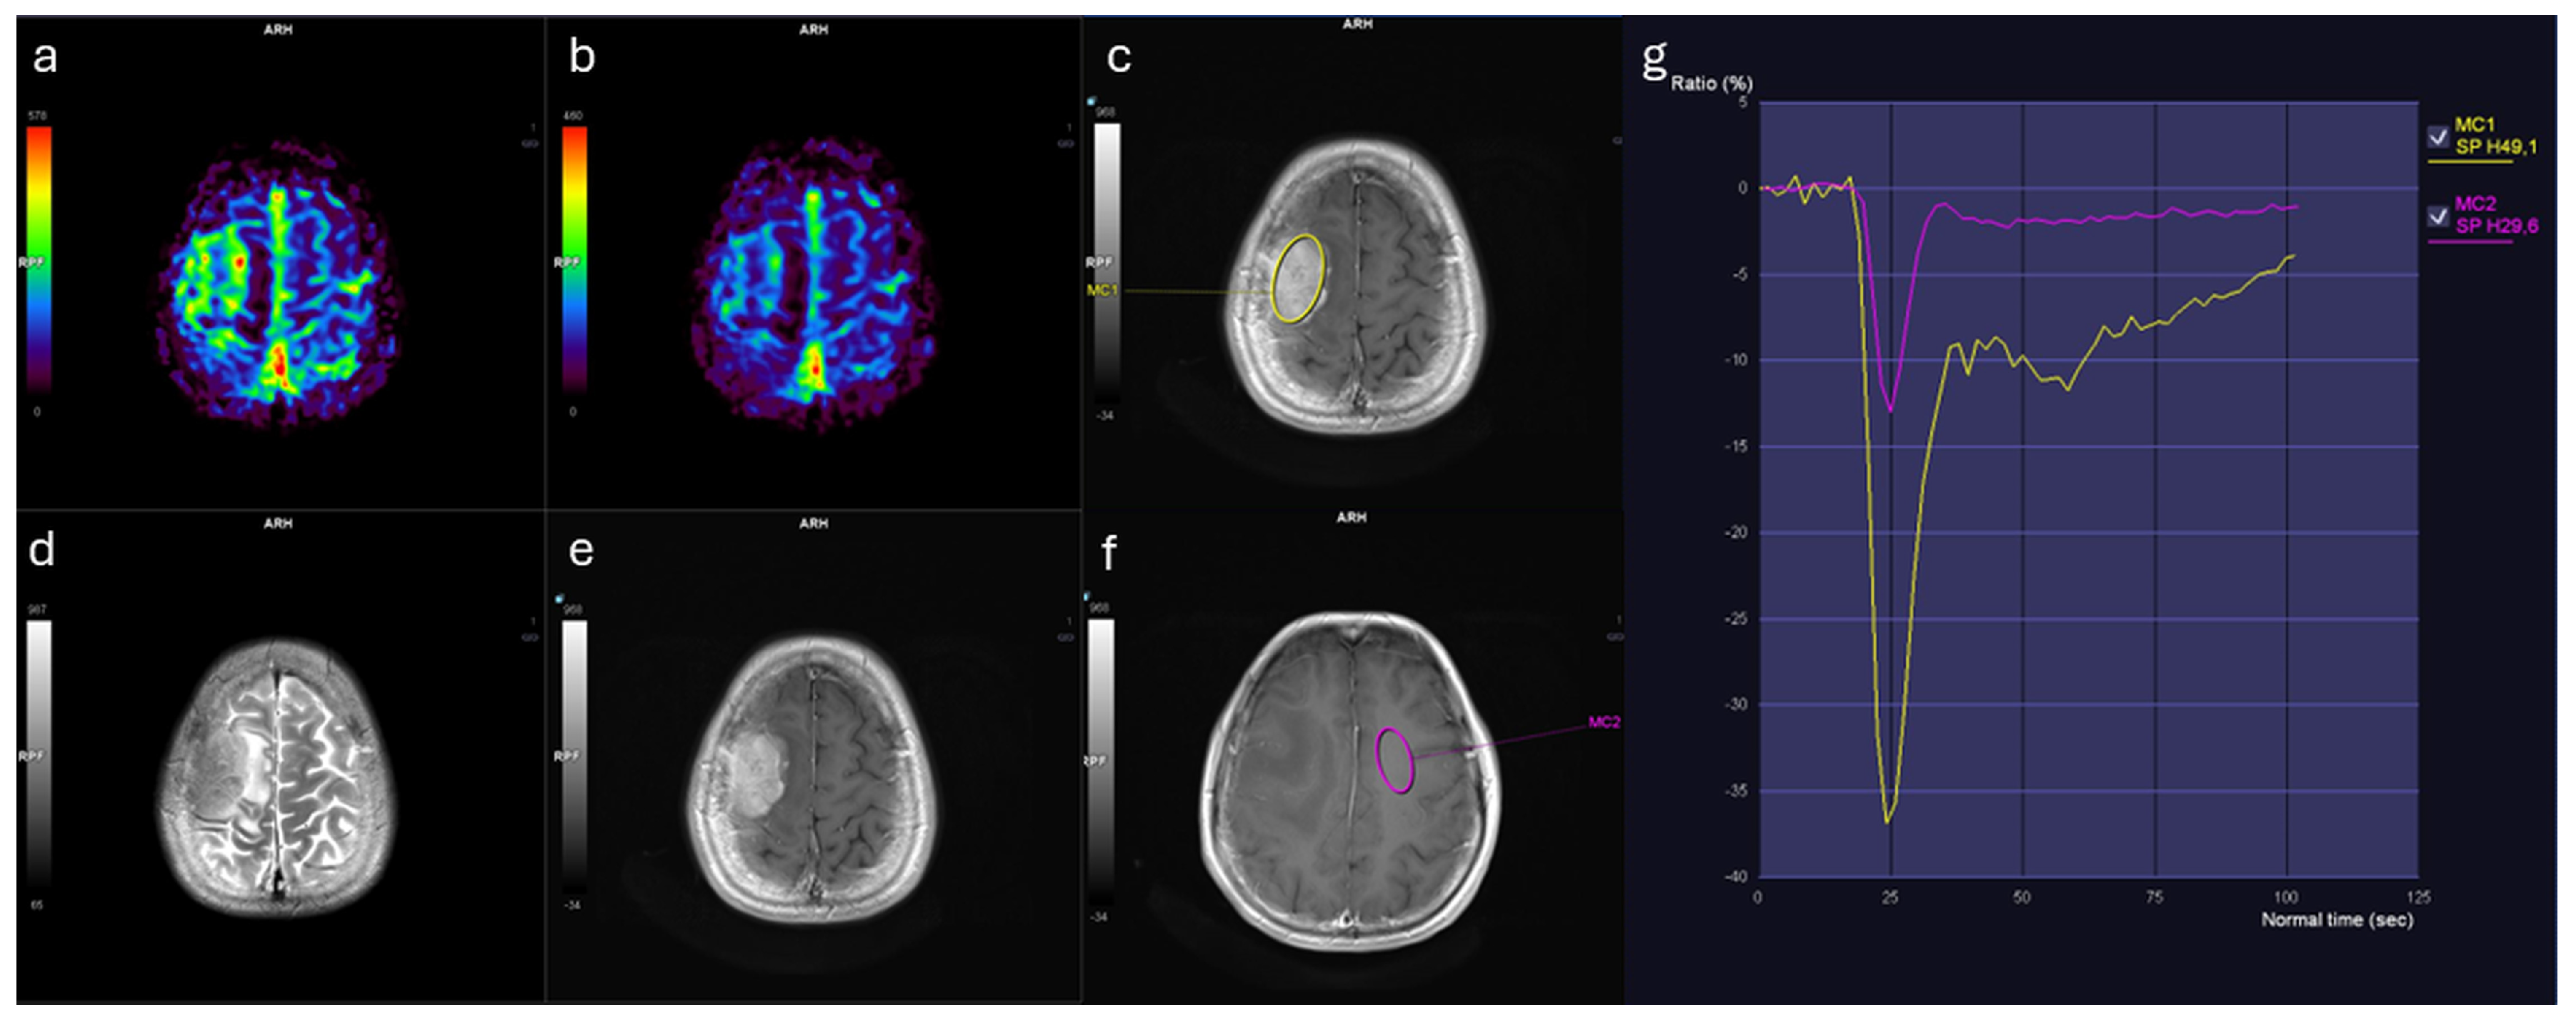

Similarly, rCBF_mean values were markedly elevated in meningiomas (3.44 [IQR: 2.11]) relative to IDMs (2.02 [IQR: 1.10], p < 0.001) (Table 1). Both rCBF_mean and rCBV_mean demonstrated large effect sizes (Cohen’s d > 1.1; η2 ≈ 0.35), indicating marked separation between groups. In contrast, no significant differences were observed between groups in terms of ADC_lesion_mean, rWiT, rPSR, or wash-out slope (Figure 1). Representative perfusion maps and time–signal intensity curves for IDM and meningioma lesions are shown in Figure 2 and Figure 3.

Figure 2. Brain MRI findings in a female patient with solitary IDM from breast cancer. (a) Relative cerebral blood volume (rCBV) map shows mildly increased perfusion. (b) Relative cerebral blood flow (rCBF) map demonstrates corresponding flow increase. (c) Contrast-enhanced T1-weighted image with region of interest (ROI, yellow contour) placed within the enhancing lesion. (d) T2-weighted image reveals lesion morphology. (e) Contrast-enhanced T1-weighted image illustrates enhancement pattern. (f) Contrast-enhanced T1-weighted image with ROI in contralateral normal-appearing white matter (pink contour). (g) Time–signal intensity curves: lesion (yellow curve) shows altered contrast dynamics compared to white matter (pink curve).